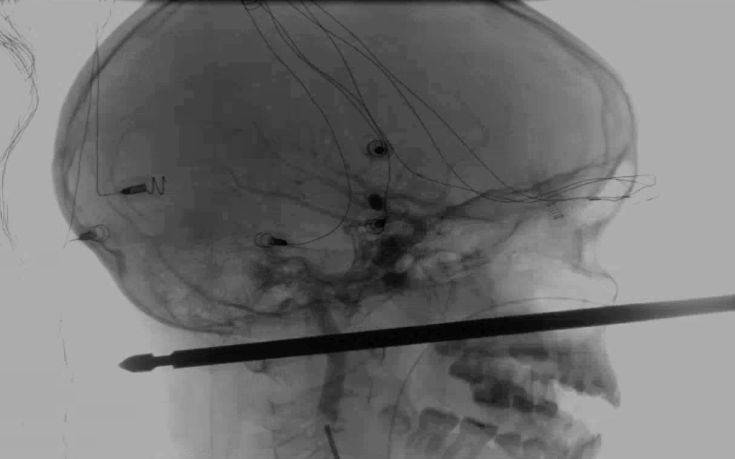

Σαν από θαύμα αναρρώνει ένα 10χρονο αγόρι από το Μιζούρι, το οποίο έπεσε από δεντρόσπιτο και καρφώθηκε σε ένα μεταλλικό ραβδί, που χρησιμοποιείται για σουβλάκια.

Το μέταλλο διαπέρασε τον κεφάλι του Xavier Cunningham αλλά δεν άγγιξε τα μάτια, τον εγκέφαλο, τον νωτιαίο μυελό και τα πιο σημαντικά αιμοφόρα αγγεία.

Η ιατρική ομάδα κατάφερε με επιτυχία να αφαιρέσει το ραβδί, το οποίο μάλιστα ήταν τετράγωνο και όχι στρογγυλό, κάνοντας την επέμβαση ακόμα πιο δύσκολη ακριβώς επειδή είχε γωνίες.